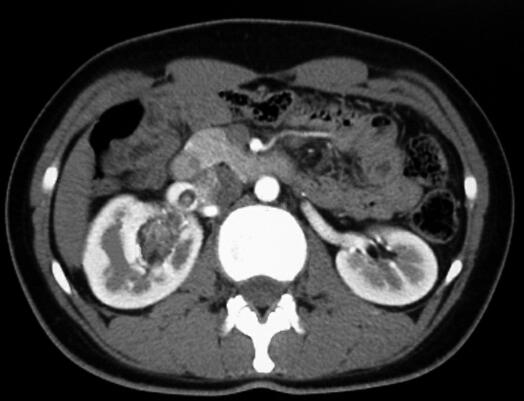

CT平扫:右肾盂旁可见一个不规则团块状混杂密度影,大小4.5cm×2.9cm×1.9cm,最低密度CT值为-40HU。增强扫描病变组织部分明显强化,最高CT值达97HU。增强后显示病变主要位于肾窦,并紧贴肾血管走行,一部分病变组织延伸至肾静脉内,一部分病灶压迫肾盂并与肾实质分界不清,右肾上、中盏受压变形(图1~图4为该肿瘤的部分CT扫描图像)。

图2增强(皮髓质期)扫描病变组织部分明显强化,最高CT值达97HU

图3增强扫描(实质期)显示病变紧贴肾血管走行,肾静脉内可见瘤栓